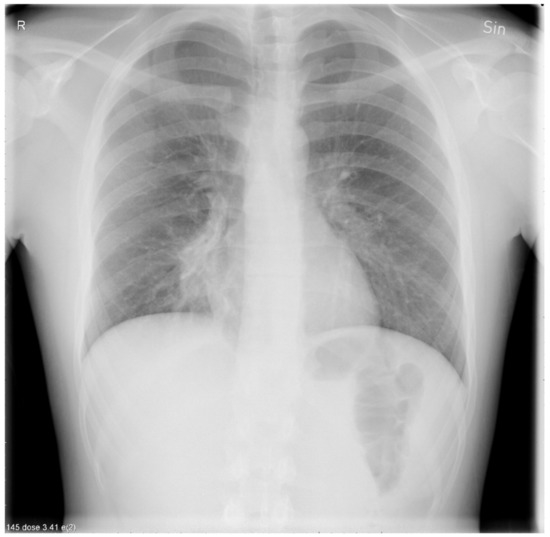

A chest X-ray revealed a right-sided lower perihilar infiltrate radiating towards the lower right lobe consistent with atypical pneumonia (Figure 4).

Figure 4.

A chest X-ray showing a right-sided lower perihilar infiltrate radiating towards the lower right lobe.